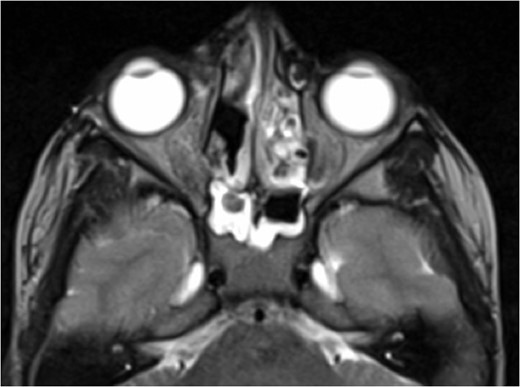

A 6-year-old boy with a background of asthma presented to a tertiary paediatric unit in May 2016 with a 3-day history of right eye pain, proptosis and erythema under the care of the ENT team. A provisional diagnosis of a periorbital cellulitis was made secondary to ethmoid sinusitis and management with intravenous antibiotics (ceftriaxone), intranasal steroids, saline douches and topical oxyxlometazoline was initiated. Ophthalmological assessment demonstrated normal colour vision, acuity and light reflexes bilaterally but also proptosis-related ophthalmoplegia. Computed tomography (CT) imaging of the orbits and paranasal sinuses demonstrated complete opacification of the right-sided paranasal sinuses and compromise of the right frontal and ostiomeatal unit. In addition there was an expansile abnormality centred on the ethmoidal labyrinth with bony remodelling of the lamina papyracea and a subperiosteal collection adjacent to the medial orbital wall (Figs 1 and 2). The most likely diagnosis was felt to be an infective process with mucopyocele formation complicated by a subperisoteal post-septal collection. An MRI scan with gadolinium of the orbits and sinuses confirmed the unilateral pattern of sinus opacification within the right frontal, ethmoids and maxillary sinus. The lesion demonstrated multiple fluid–fluid levels and peripheral enhancement (Figs 3 and 4). The patient was treated by endoscopic drainage of the lesion, which revealed only blood. He initially had some improvement of his proptosis but recurred within a few days and so further, more extensive endoscopic debridement was performed.

Axial T1 post-contrast sequence with fat suppression demonstrating peripheral enhancement (white arrows) but no internal or solid enhancing components to suggest that this is a secondary ABC.